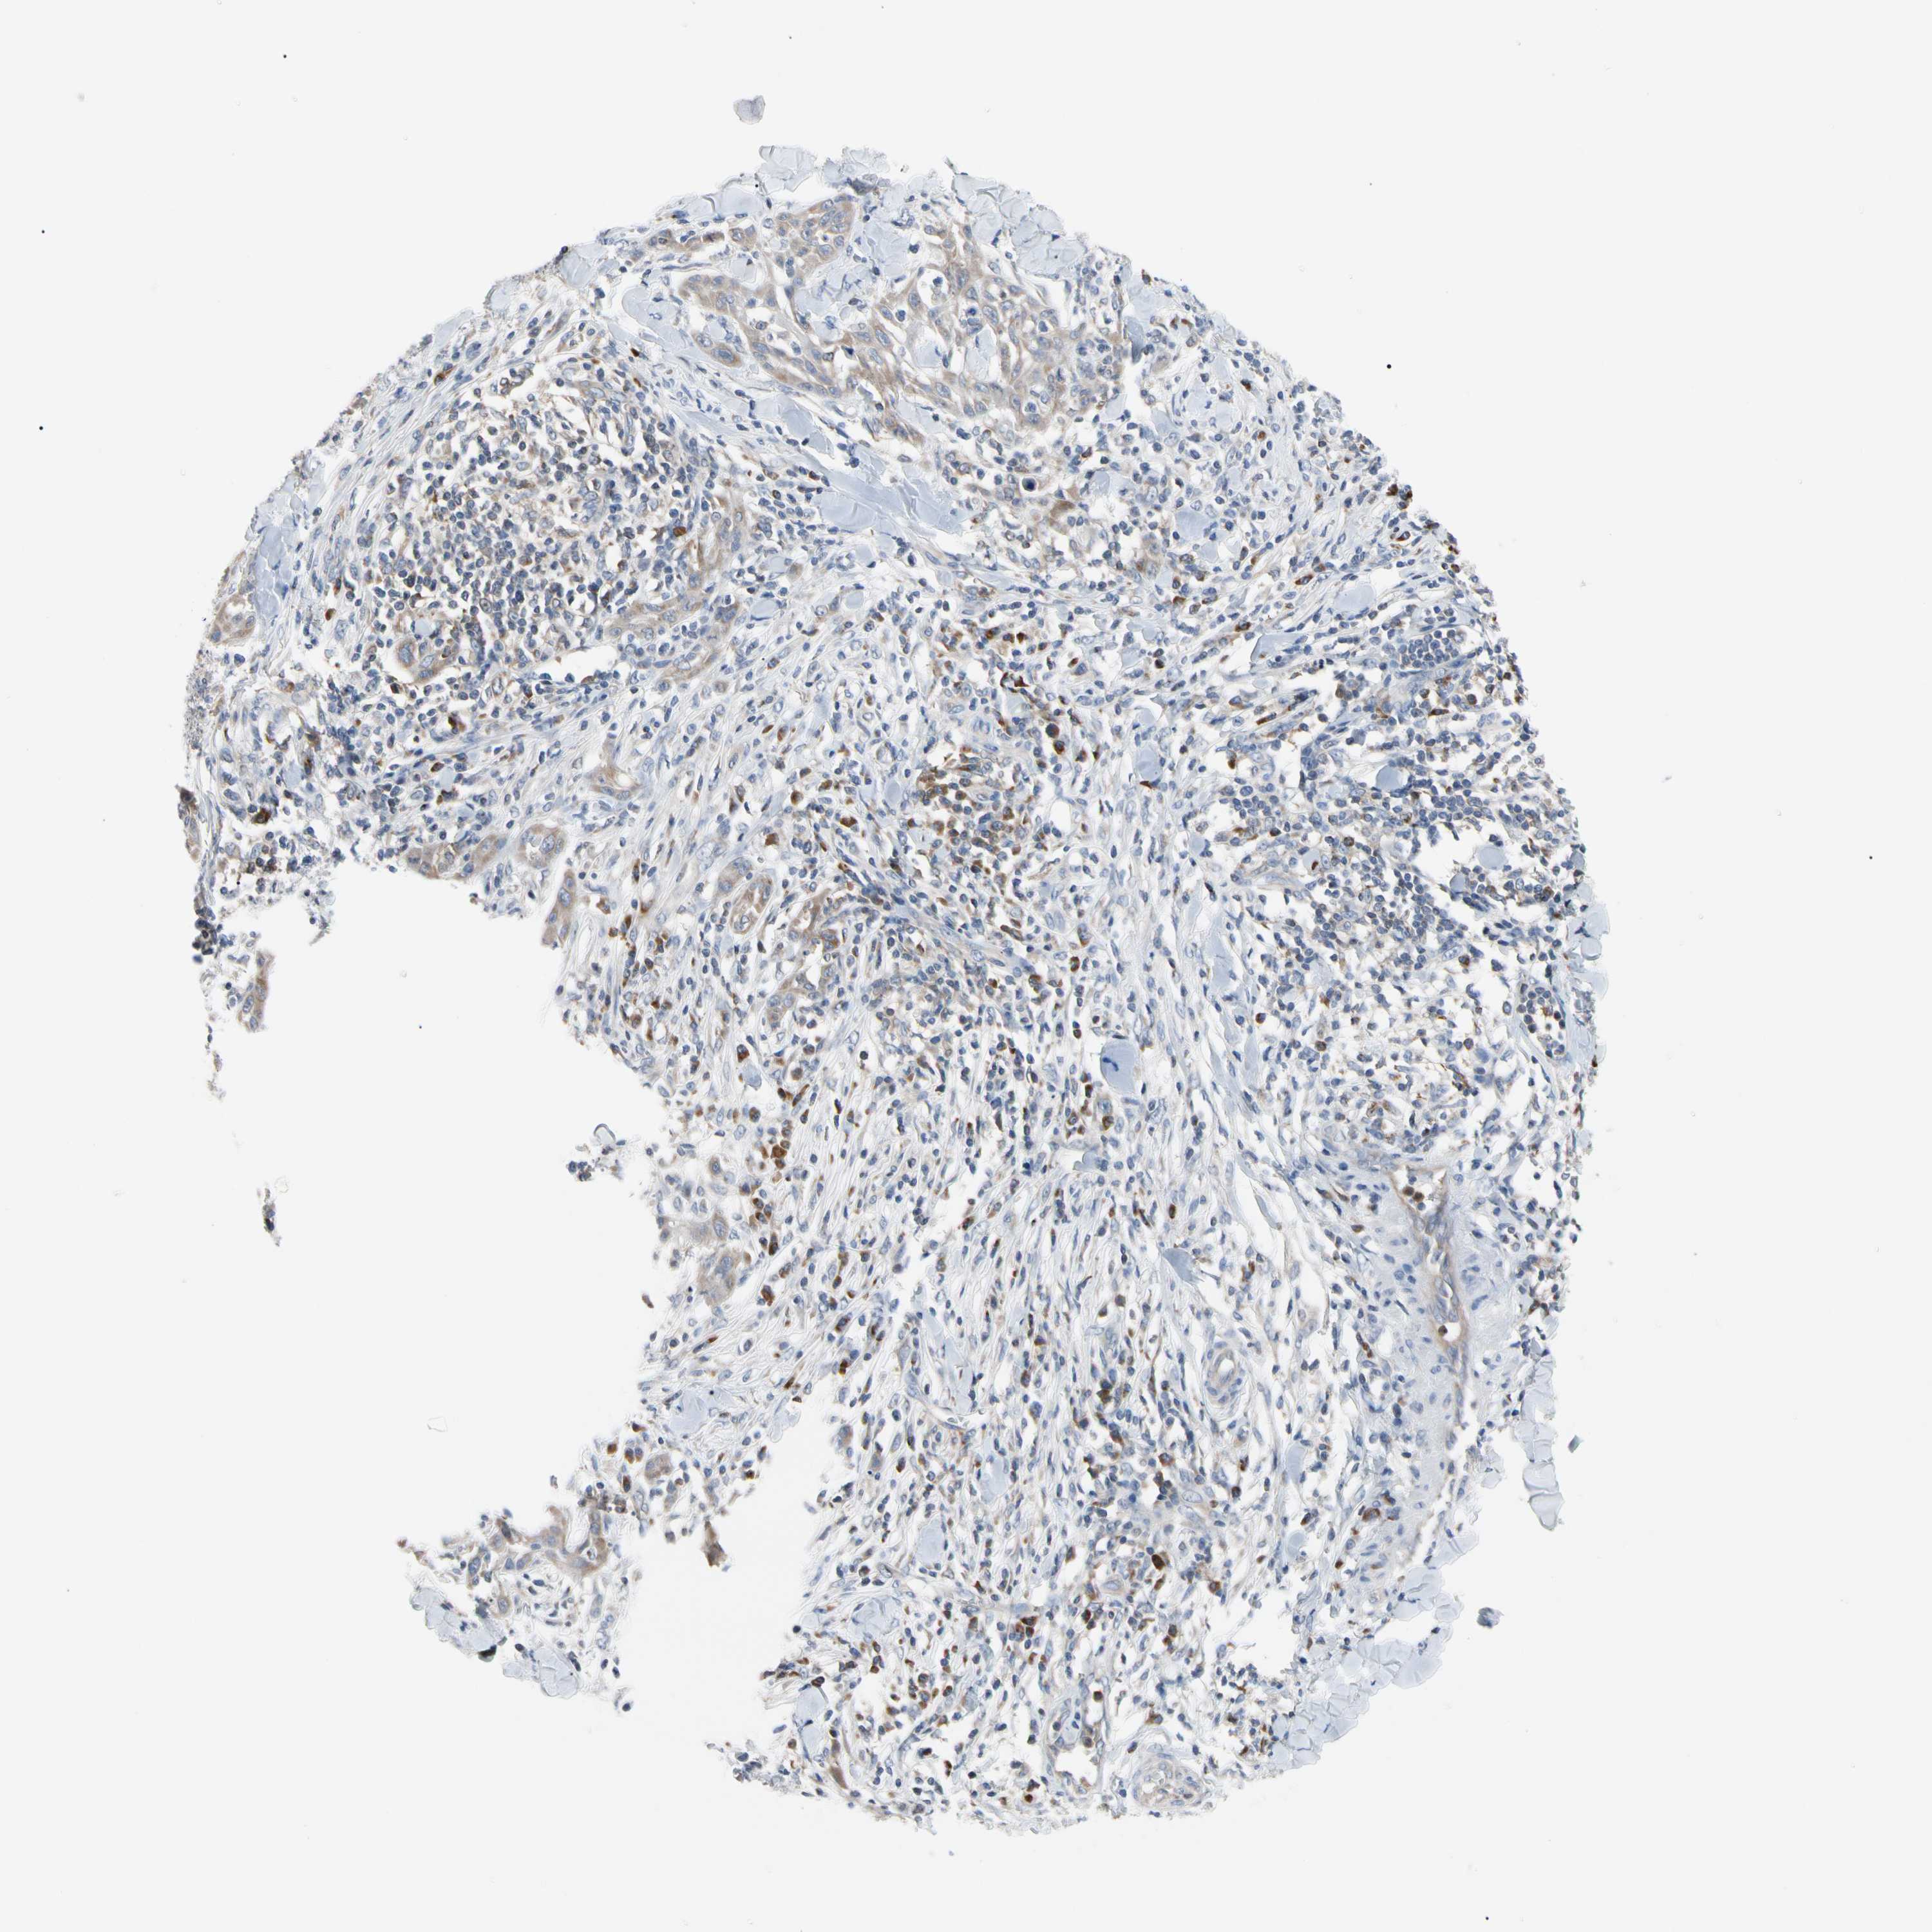

SKIN CANCER - Protein expressioni

A mouse-over function shows sample information and annotation data. Click on an image to view it in a full screen mode. Samples can be filtered based on level of antibody staining by selecting one or several of the following categories: high, medium, low and not detected. The assay and annotation is described here.

Antibody stainingi

Antibody staining in the annotated cell types in the current human tissue is reported as not detected, low, medium, or high, based on conventional immunohistochemistry profiling in selected tissues. This score is based on the combination of the staining intensity and fraction of stained cells.

Each image is clickable and will lead to virtual microscopy that enables deeper exploration of all samples and also displays staining intensity scores, fraction scores and subcellular localization as well as patient and tissue information for each sample.

Staining

High

Medium

Low

Not detected

Intensity

Strong

Moderate

Weak

Negative

Quantity

>75%

75%-25%

<25%

None

Location

Nuclear

Cytoplasmic/membranous

Cytoplasmic/membranous,nuclear

Squamous cell carcinoma, NOS

Squamous cell carcinoma, metastatic, NOS

Basal cell carcinoma